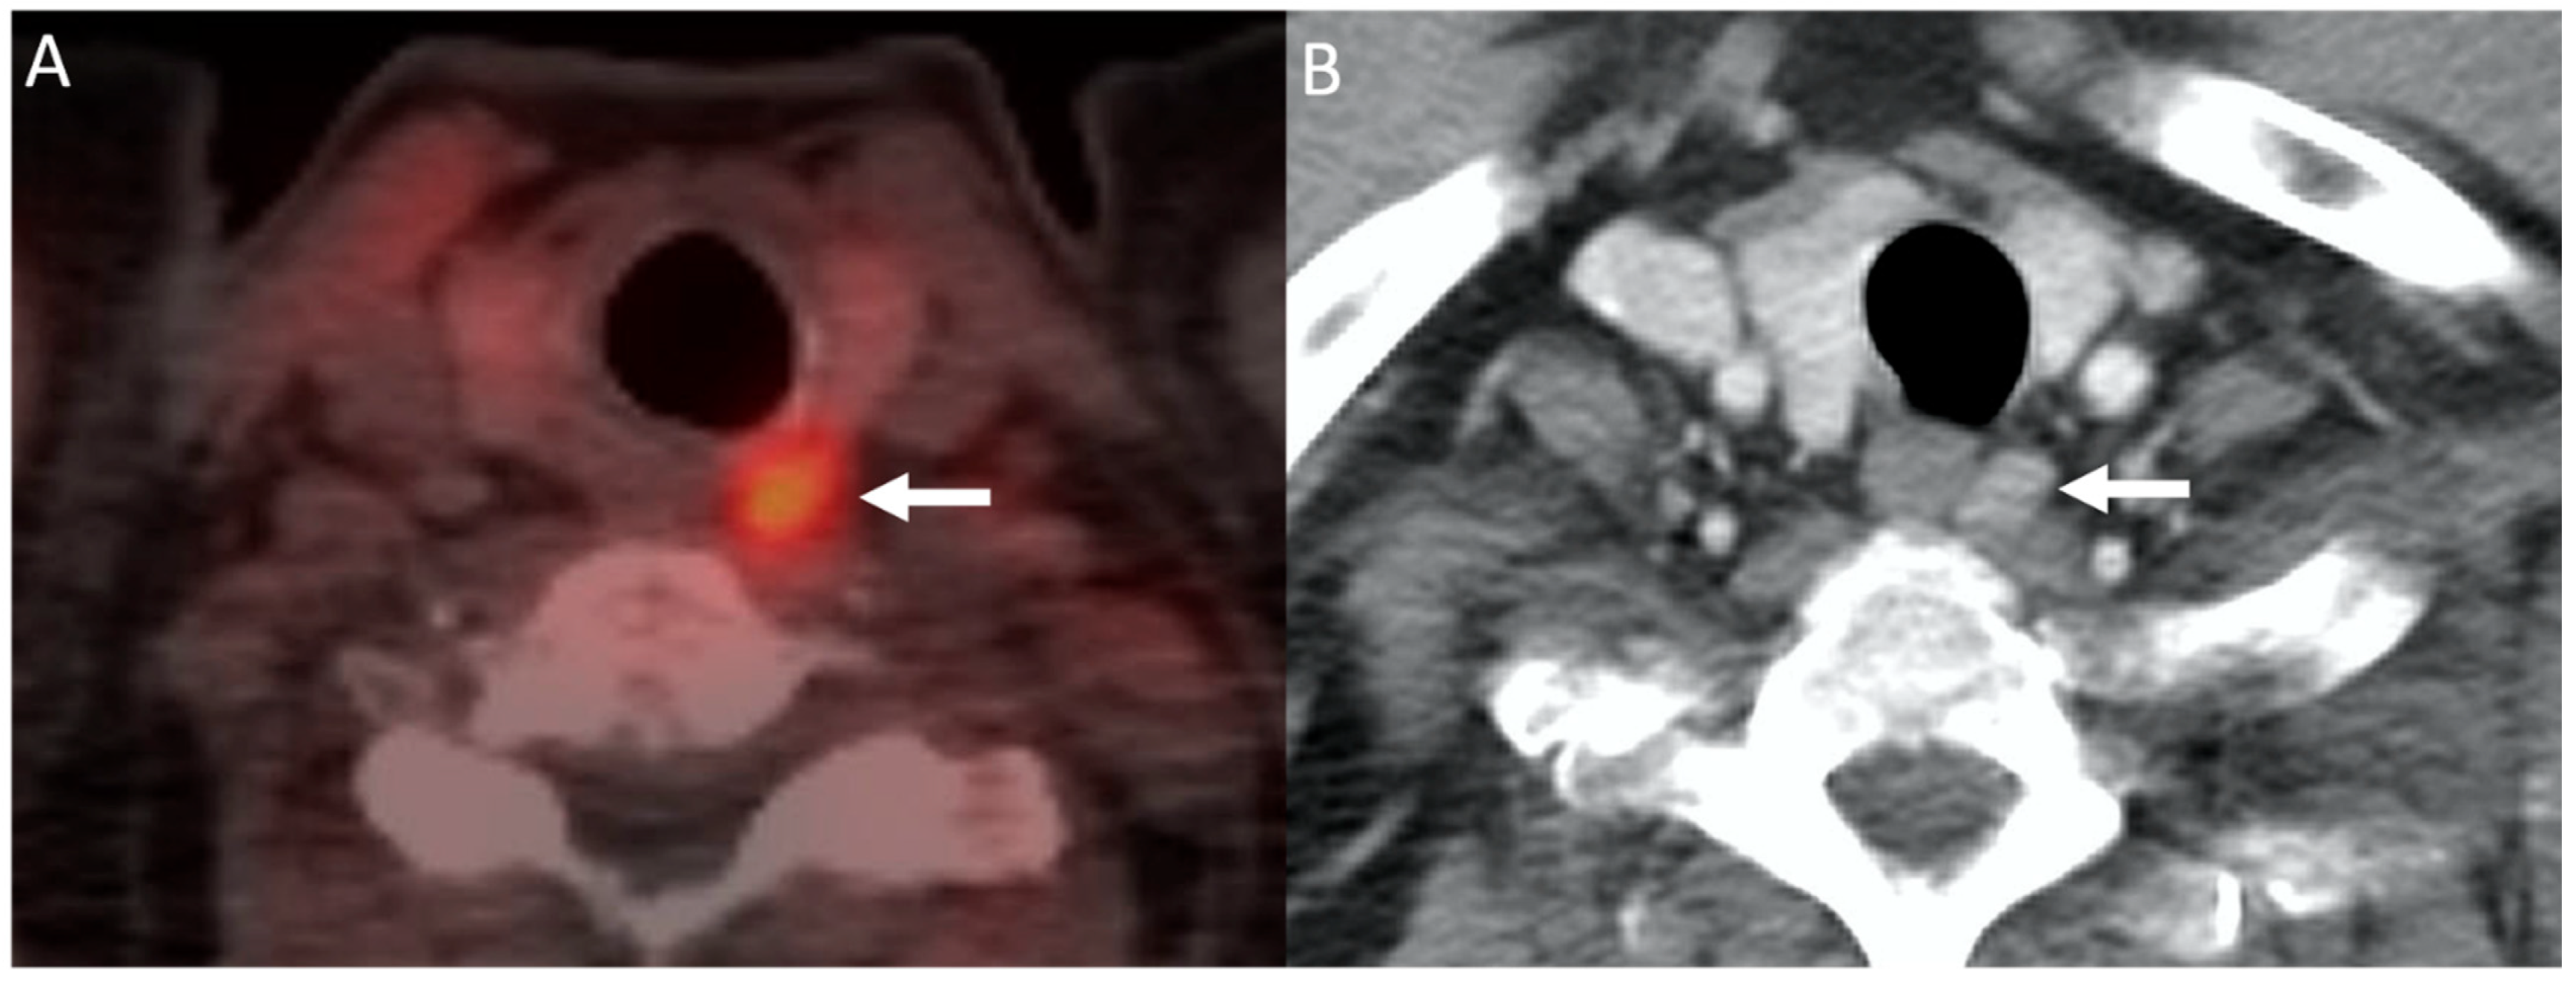

Since FCH is more widely used than 11C-Choline, which requires an on-site cyclotron, we will discuss PET imaging using FCH. Imaging acquisition is typically performed 60 min after intravenous injection of FCH with the patient in a supine position on the PET/CT scanner. For interpretation, visual analysis of focal lesions detected with FCH-PET/CT is performed and maximum standardized uptake value (SUVmax) can be used for semiquantitative interpretation [73]. Focal uptake of radiotracer can be seen within a solitary (Figure 6) or multiple hyperfunctioning parathyroid glands in the thyroid bed or in an ectopic location (such as the mediastinum) [72]. The SUVmax of a parathyroid gland is usually greater than four times that of adjacent thyroid tissue [71].

Figure 6.

Choline PET/CT: 68-year-old man with hypercalcemia and history of prostate cancer. 11C-Choline-PET/CT image (A) demonstrating focal choline uptake within a nodule posterior to the left mid thyroid gland (arrow). Subsequent contrast-enhanced CT (B) demonstrating a corresponding enhancing nodule. The patient was subsequently taken for surgical resection which revealed a left upper parathyroid adenoma.